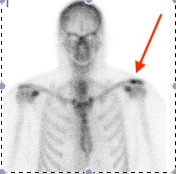

Acromioclavicular joint osteolysis

Bone Scan